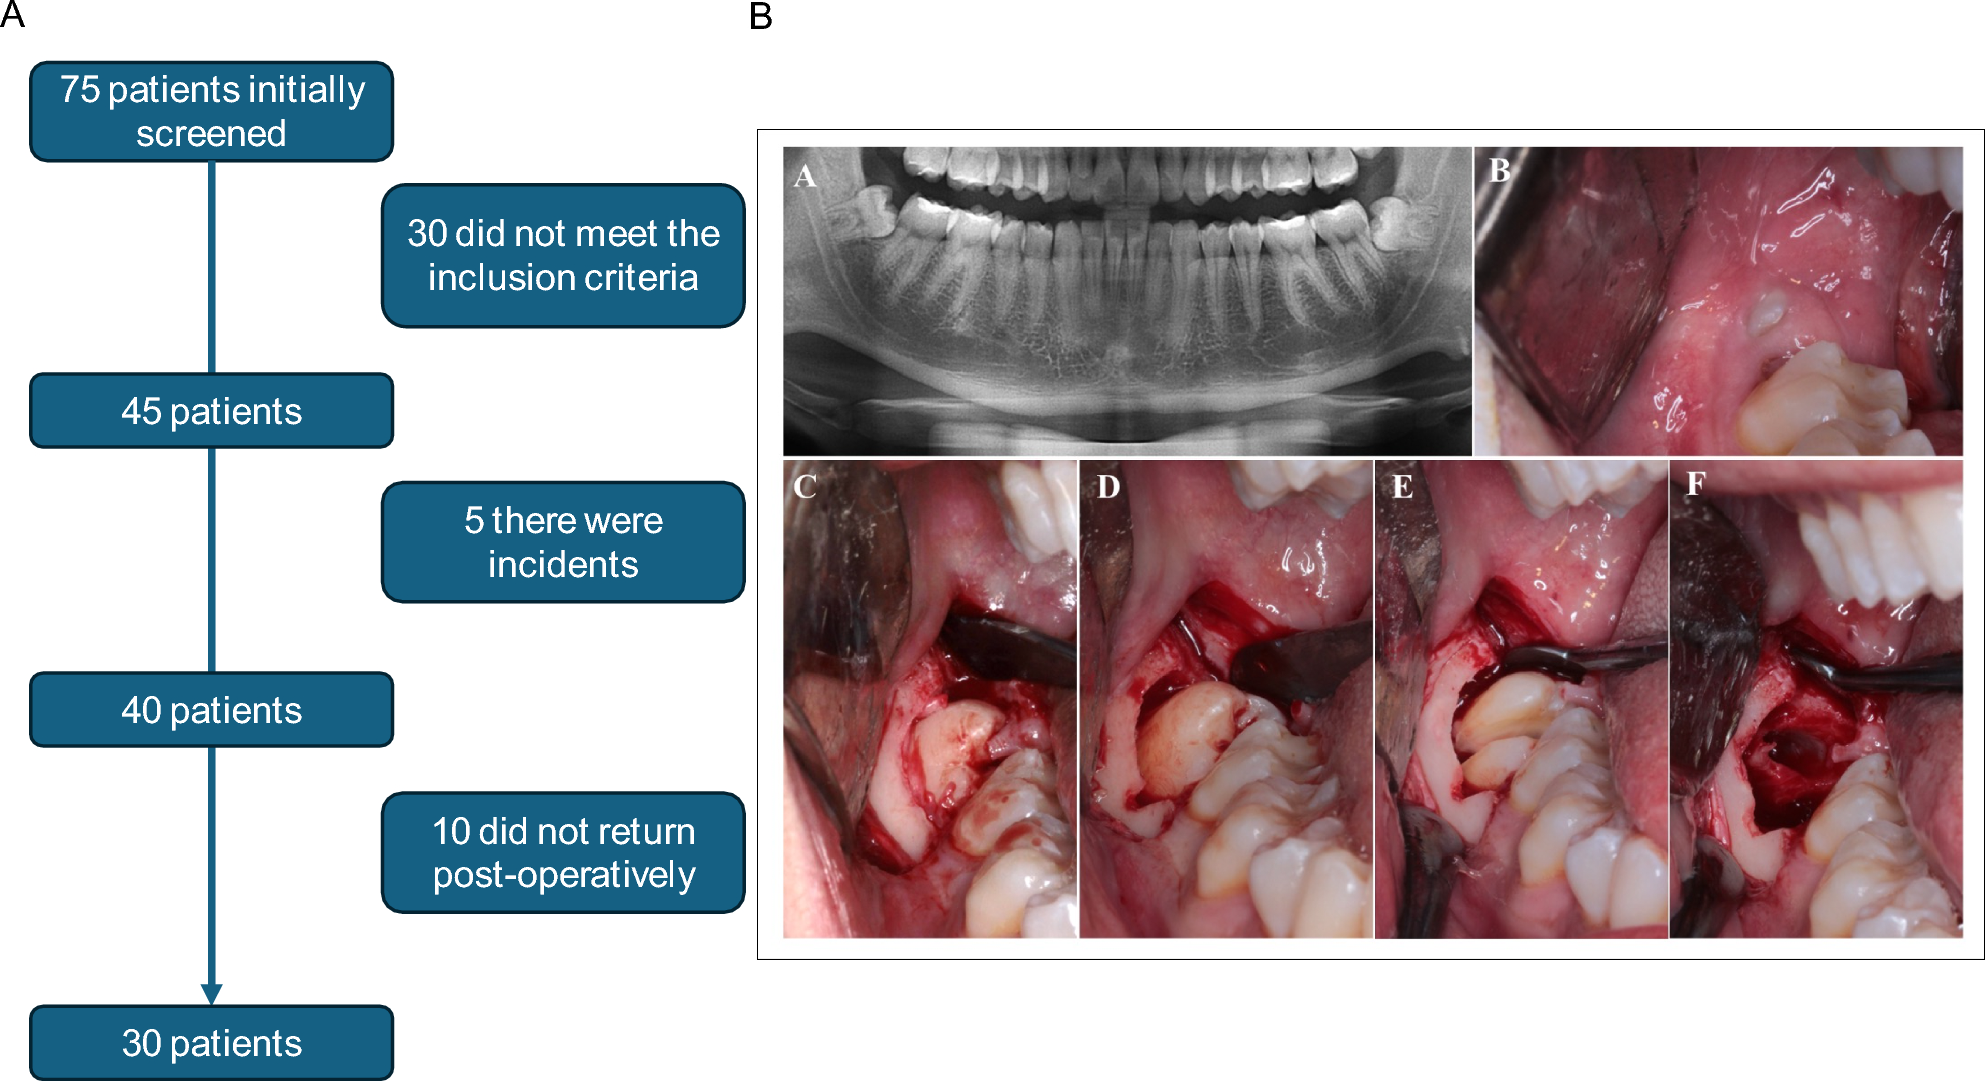

Fig. 1

A- Flowchart of the individuals selected according to CONSORT guidelines. Initially, 75 patients were screened; of these, 30 did not meet the inclusion criteria, resulting in 45 eligible patients. Among them, 5 experienced postoperative complications and were excluded, totaling 40 patients who underwent the surgical procedure. Of these, 10 did not attend the postoperative follow-up, thus 30 patients were included in the final analysis. B-Illustrative sequence of the standardized surgical procedure performed for the removal of impacted mandibular third molars. The images represent: (A) panoramic radiograph showing a patient eligible for the study; (B) initial clinical view of the surgical site; (C) exposure of the anatomical structure of interest; (D) performance of the osteotomy; and (E) tooth sectioning (odontosection). All procedures were carried out by a trained surgical team, following a standardized protocol to ensure consistency and reproducibility across cases.